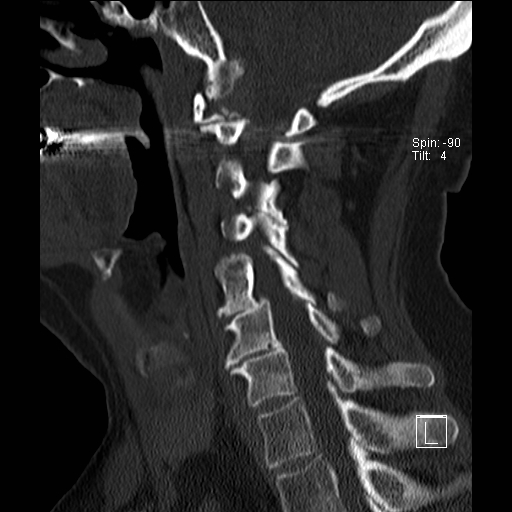

Trật khớp đội – trục

Cột sống cổ thường bị ảnh hưởng trong viêm khớp dạng thấp và có thể biểu hiện dưới dạng mất vững khớp đội – trục, trật khớp dưới trục hoặc lồng nền sọ kèm theo sụt lún sọ não.

Sụt lún sọ não xảy ra khi mỏm răng xâm lấn vào lỗ chẩm.

Trật khớp đội – trục là một biến chứng quan trọng và có thể đe dọa tính mạng của viêm khớp dạng thấp. Tình trạng này được xác định khi khoảng cách giữa mỏm răng C2 và cung đốt đội vượt quá 3 mm. Nguyên nhân là do lỏng lẻo dây chằng do viêm.

Mất vững tại khớp này có thể gây ra nhiều triệu chứng thần kinh do chèn ép tủy sống.

Hình ảnh

Khi cúi cổ, khoảng cách giữa mỏm răng và mặt sau cung trước đốt đội bị giãn rộng (14 mm) (bình thường ≤3 mm).